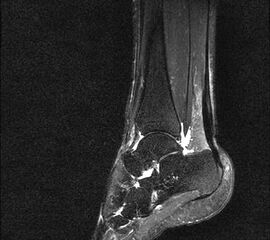

Hier befindet sich ca. 3-5 cm proximal des Tuber calcanei ein als „kritische Zone“ benannter Bezirk, der durch eine ungünstige arterielle Blutzufuhr gekennzeichnet ist (letzte Wiese). Hier finden sich häufig spindelförmige Schwellungen, die bei MRT-Diagnostik nicht selten partielle Nekrosen und Partialrupturen der Achillessehne aufweisen (Abb. 14).

Unabhängig davon können insbesondere chronische Insertionstendinosen der Achillessehne von Partialrupturen (Abb. 15) und erosiven Läsionen des dorsalen Fersenbeines begleitet sein.

Die sonographische Diagnostik eignet sich primär zur Erkennung schmerzhafter Prozesse im Verlauf der Achillessehne und kann bei Bedarf durch Röntgen bzw. MRT ergänzt werden. Besonders bei längeren Verläufen und kräftigen spindelförmigen Schwellungen (>9mm, Normwert <5mm) im Bereich der kritischen Zone sollte ein MRT zum Ausschluss von Nekrosezonen und Partialrupturen vor Therapiebeginn veranlasst werden. Die sonographisch leicht zu erfassende Veränderung der Sehnendicke im mittleren Sehnenanteil ist ein guter Indikator für die Schwere der Erkrankung und die Beurteilung des Behandlungsverlaufes. Die sichtbaren Veränderungen am distalen knöchernen Ansatz der Sehne sind diskreter.

Insbesondere bei größeren Partialrupturen (Abb. 14) sollten operative Verfahren erörtert werden. Kleinere Partialrupturen sind der ESWT gut zugänglich, wie die beiden nachfolgenden Beispiele zeigen: